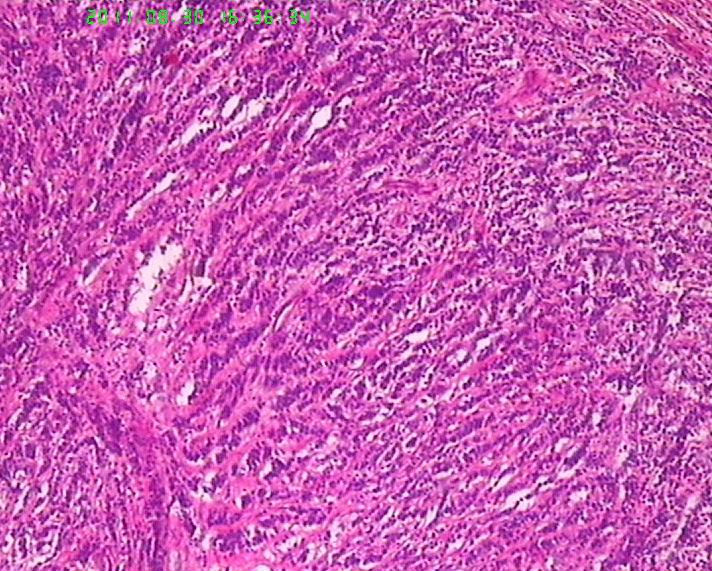

此例男,65岁。术前胃镜活检学生报告“低分化腺癌”,行手术治疗。术后见胃体后壁小弯测溃疡性肿物直径6.5cm,周围隆起质地硬,肉眼侵及肌层。镜下所见如图,似乎不是腺癌,是否是类癌??但核分裂很活跃,不见核仁。胃周淋巴结未检出转移。请老师们帮忙指正。学生感激。

• 焦急:胃肿物,请老师帮看下。图1

图1

肿瘤呈流水线样排列,有腺样结构,核分裂像多见,从这些来说至少不是类癌了,如果是神经内分泌肿瘤,那也应该是神经内分泌癌了,此例可能为腺癌伴神经内分泌分化,需做免疫标记证实是否有神经内分泌分化。

若诊断管状腺癌,其中未见任何“管腺”形成迹象,故应诊断为“未分化腺癌”。但学生有以下疑问:1、为何肿瘤与正常胃粘膜交界处不见“非典型增生腺体”移行,而是截然交界。交界处可见淋巴细胞浸润。2、为何肿瘤浸润肌层的界面圆顿,如同“疣状癌”的膨胀性推挤生长。3、未分化腺癌恶性程度高,而为何胃周淋巴结检出二十余枚均未见转移。

书上说有一种分化差的管状腺癌称为实体癌,此例会是吗,学生没见过!